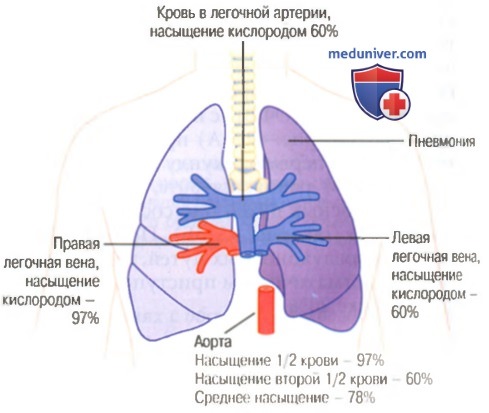

Схемы дыхания: Пневмоторакс на изображениях